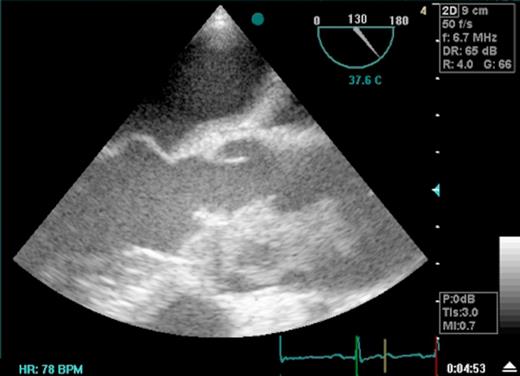

On transfer he was haemodynamically stable in sinus rhythm and clinical examination was essentially normal except for the presence of a soft systolic ejection murmur. Transthoracic echocardiography undertaken in coronary care revealed a mobile thrombus, 4.4 x 1.8cm, attached to the right coronary cusp of the aortic valve, which appeared thickened and calcified. The thrombus extended up into the ascending aorta almost to the innominate artery. The thrombus appeared to be compromising his aortic valve. Ventricular function remained well preserved. It was not possible to obtain an accurate gradient across the valve.

He was taken to theatre as an emergency. A pre-operative Transoesophageal Echocardiogram (TOE) confirmed the presence of thrombus on the aortic valve extending into the ascending aorta (Fig 1). After median sternotomy and initiation of cardiopulmonary bypass the ascending aorta was clamped at the level of the innominate artery. TOE confirmed that the clamp site was above the top level of the thrombus. The thrombus was all removed and submitted for bacteriological culture. Once the coronary ostia were identified the heart was arrested with cold blood cardioplegia. A calcified bicuspid aortic valve was excised and replaced with a 27-mm ATS open pivot heart valve. No organisms were seen on gram staining of the thrombus however following advice from the microbiological team empirical therapy with vancomycin and gentamicin was initiated. He made an uneventful postoperative recovery and was commenced on intravenous heparin after surgery until he was adequately anticoagulated with warfarin and aspirin. All cultures were negative. He was discharged from hospital on his eighth post-operative day.

Transoesophageal Echocardiogram depicting thrombus in the ascending aorta